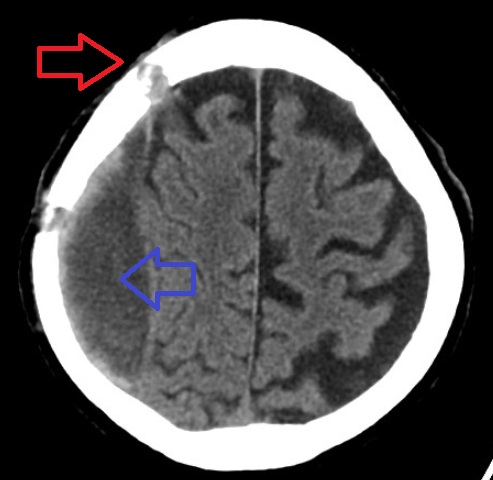

Uncal herniation is another type of herniation, in which the temporal lobe uncus is displaced under the tentorium cerebelli.

In an uncal herniation, compression of cranial nerve III, the oculomotor nerve, causes the ipsilateral eye to move “down and out” and the pupil to dilate.

Other potential complications of herniation include:

- Infarction of the occipital lobe or the opposite homonymous hemianopia are caused by compression of the posterior cerebral artery

- Infarction occurs when the anterior cerebral artery is compressed